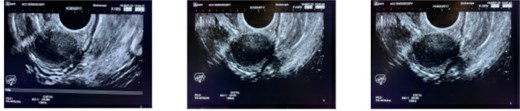

CT scan and colonoscopy revealed a 2-cm submucosal lesion located 23 cm from the anal verge (Fig. 1). Endoscopic ultrasound demonstrated a homogeneously hypoechoic lesion with smooth margins, originating from the muscularis mucosa (Fig. 2). No regional lymphadenopathy was identified. The features were most consistent with a leiomyoma, with gastrointestinal stromal tumour (GIST) considered less likely.

Endoscopic ultrasound demonstrating a homogeneously hypoechoic, smooth-margined lesion arising from the muscularis layer. Endoscopic tattooing for surgical localization, lesion marked at 23 cm from the anal verge with three tattoo spots placed 3 cm distal to the lesion.